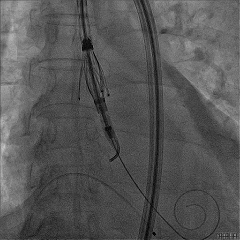

TAVR手术过程

主动脉瓣大量反流

回撤导引鞘,定位键顺利展开

输送器调弯